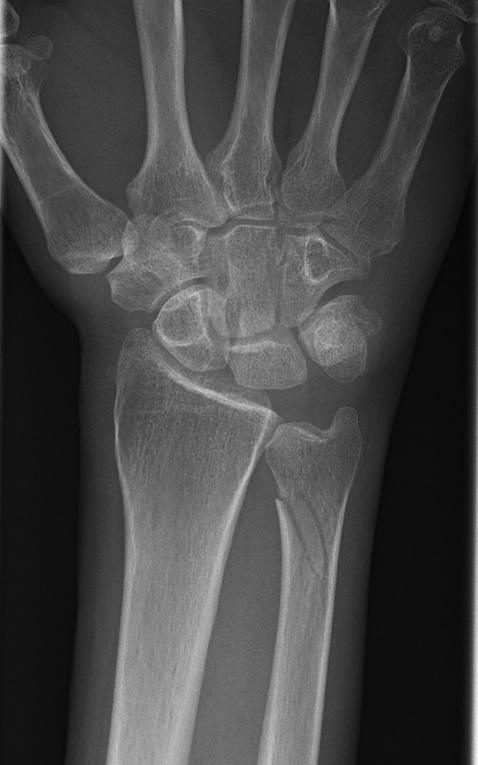

Galeazzifraktur: fraktur på distala tredjedelen av radius och samtidig luxation av ulnahuvudet (vid DRU-leden).

Galeazzifraktur